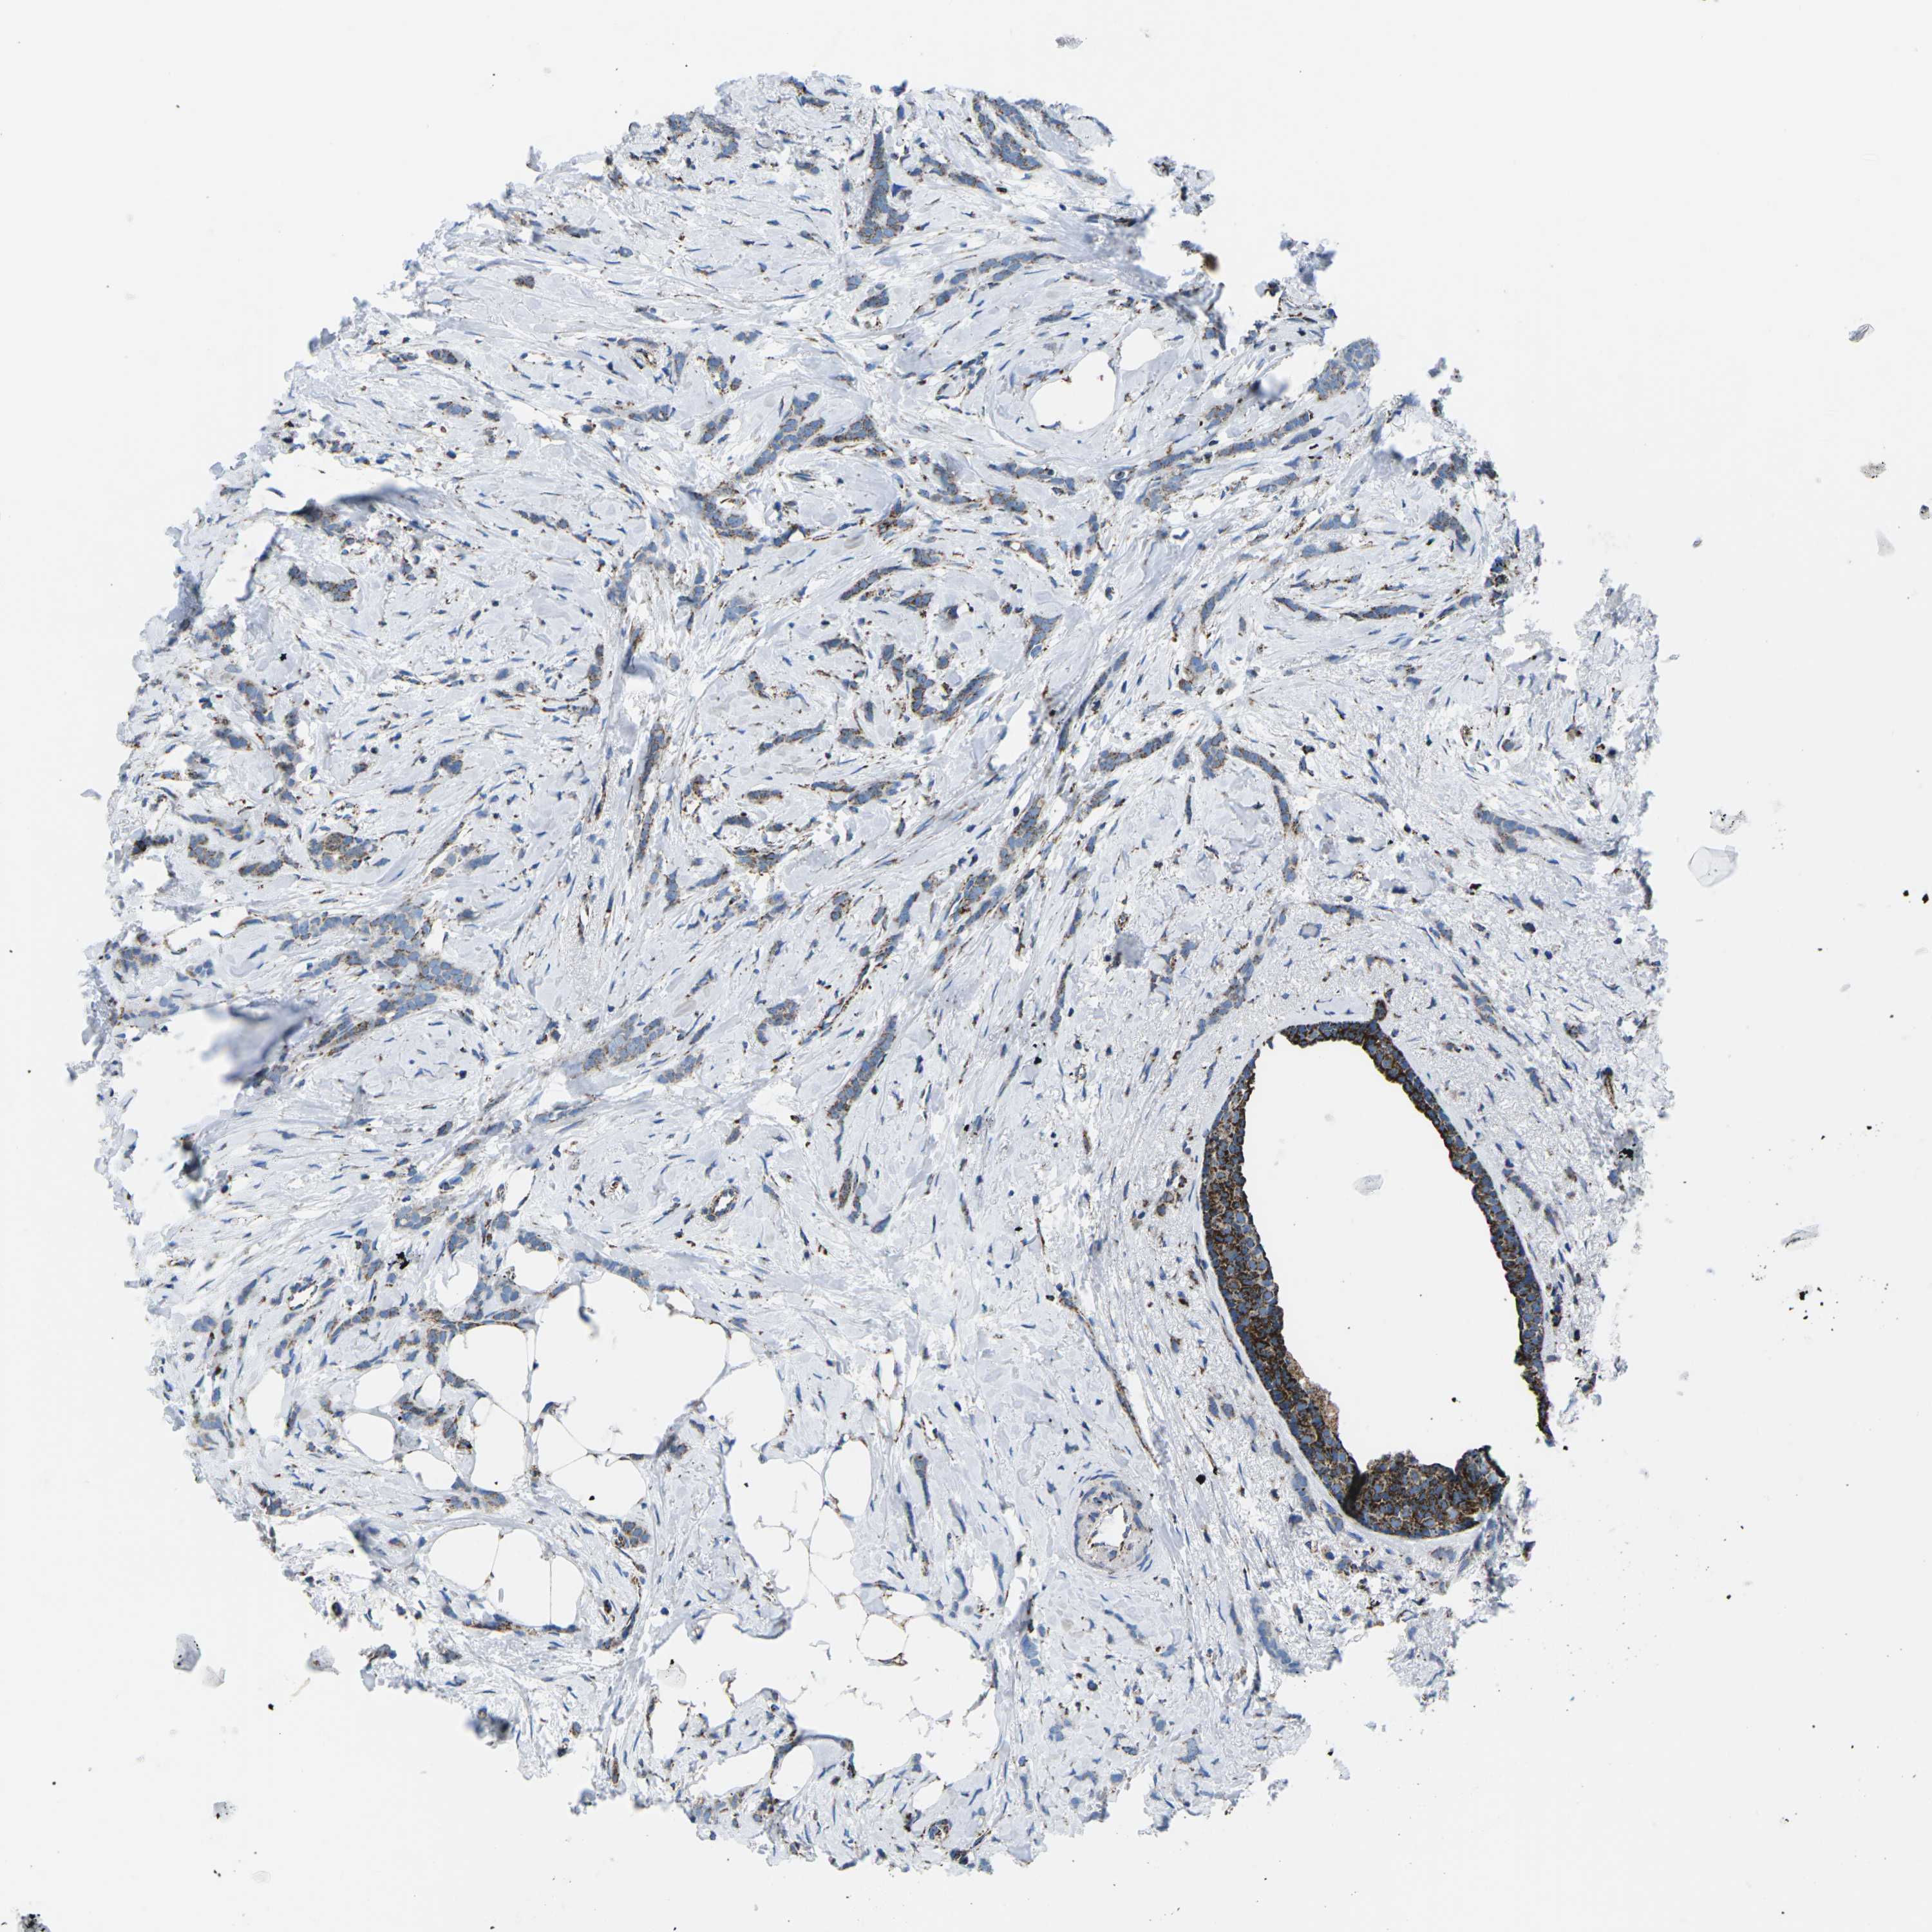

BRCA TCGA BRCA VALIDATION PROTEIN EXPRESSION

ANTIBODIES

AND

VALIDATION